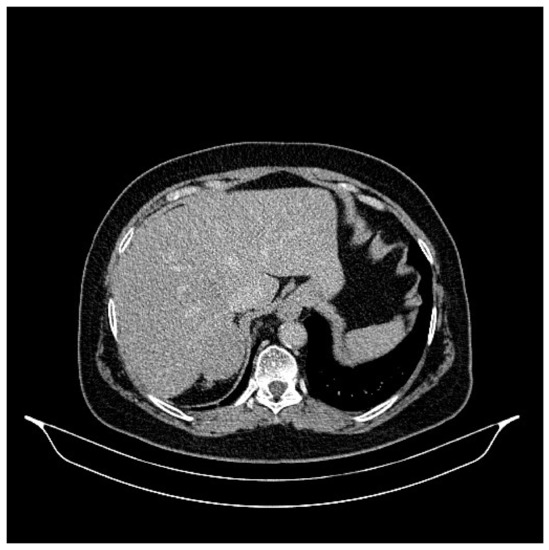

2. Case Presentation